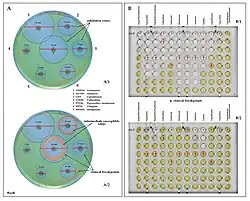

Quorum sensing

P. aeruginosa is an opportunistic pathogen with the ability to coordinate gene expression in order to compete against other species for nutrients or colonization. Regulation of gene expression can occur through cell-cell communication or quorum sensing (QS) via the production of small molecules called autoinducers that are released into the external environment. These signals, when reaching specific concentrations correlated with specific population cell densities, activate their respective regulators thus altering gene expression and coordinating behavior. P. aeruginosa employs five interconnected QS systems – las, rhl, pqs, iqs, and pch – that each produce unique signaling molecules.[66] The las and rhl systems are responsible for the activation of numerous QS-controlled genes, the pqs system is involved in quinolone signaling, and the iqs system plays an important role in intercellular communication.[67] QS in P. aeruginosa is organized in a hierarchical manner. At the top of the signaling hierarchy is the las system, since the las regulator initiates the QS regulatory system by activating the transcription of a number of other regulators, such as rhl. So, the las system defines a hierarchical QS cascade from the las to the rhl regulons.[68] Detection of these molecules indicates P. aeruginosa is growing as biofilm within the lungs of cystic fibrosis patients.[69] The impact of QS and especially las systems on the pathogenicity of P. aeruginosa is unclear, however. Studies have shown that lasR-deficient mutants are associated with more severe outcomes in cystic fibrosis patients[70] and are found in up to 63% of chronically infected cystic fibrosis patients despite impaired QS activity.[71]

QS is known to control expression of a number of virulence factors in a hierarchical manner, including the pigment pyocyanin. However, although the las system initiates the regulation of gene expression, its absence does not lead to loss of virulence factors. Recently, it has been demonstrated that the rhl system partially controls las-specific factors, such as proteolytic enzymes responsible for elastolytic and staphylolytic activities, but in a delayed manner. So, las is a direct and indirect regulator of QS-controlled genes.[67] Another form of gene regulation that allows the bacteria to rapidly adapt to surrounding changes is through environmental signaling. Recent studies have discovered anaerobiosis can significantly impact the major regulatory circuit of QS. This important link between QS and anaerobiosis has a significant impact on production of virulence factors of this organism.[72] Garlic experimentally blocks quorum sensing in P. aeruginosa.[73]